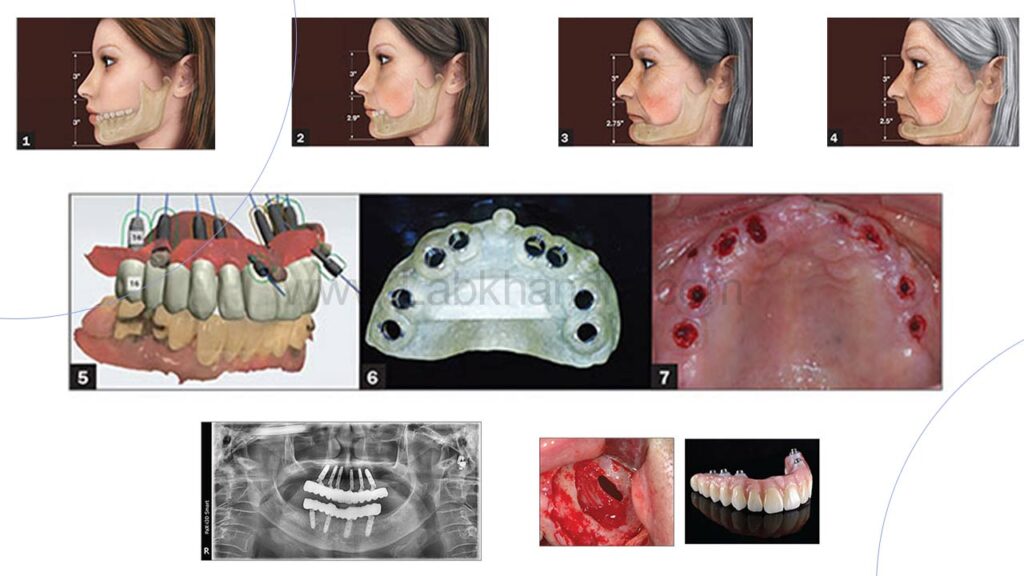

3. ساخت گاید جراحی (Surgical Guide)

در روش ایمپلنت دیجیتال، برای دقت بیشتر از گاید جراحی سفارشی استفاده می شود. گاید جراحی که با پرینتر سه بعدی یا دستگاه های پیشرفته ساخته می شود، دندانپزشک را در جایگذاری دقیق ایمپلنت هدایت می کند و خطای جراحی را کاهش می دهد.

4. کاشت پایه ایمپلنت

با استفاده از گاید جراحی، پایه ایمپلنت (فیکسچر) با حداقل برش و کمترین آسیب به بافتهای اطراف در داخل استخوان فک قرار میگیرد. به دلیل دقت بالا، مدت زمان جراحی کوتاه تر شده و بیمار درد و ناراحتی کمتری را تجربه می کند.